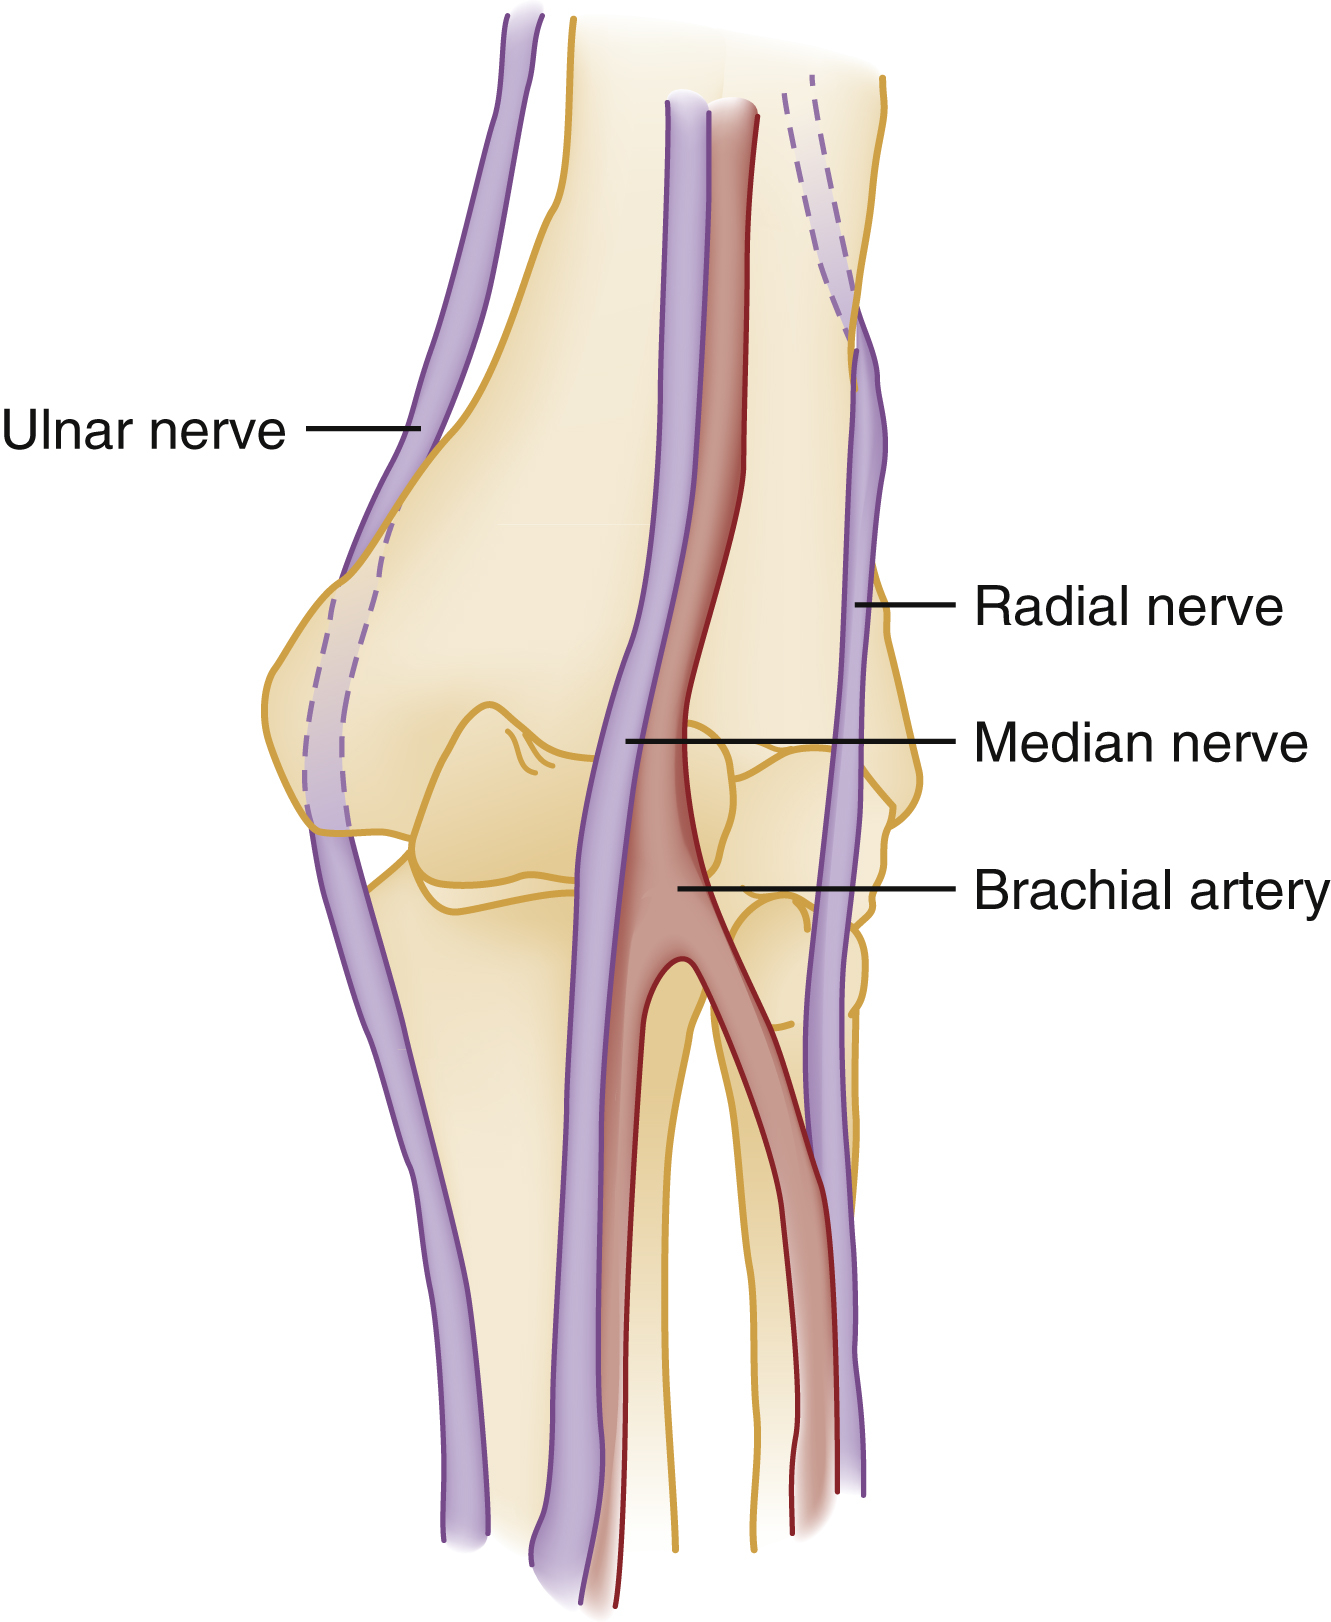

Knowledge of the relevant anatomy, mechanisms of injury, and appropriate management techniques, as well as knowing when to refer to or consult with orthopedic specialists will improve outcomes. The essential anatomy of the elbow region, as it relates to acute injury, is shown in Figs. 44.1–44.4 .

Neurovascular Structures of Elbow Region.

Volar surface of left elbow is shown.

In addition to the elbow region itself, focused examination incudes a thorough evaluation of the distal neurovascular status of the extremity. The presence of the brachial, radial, and ulnar pulses is confirmed by palpation. The ulnar pulse is more difficult to palpate than the radial pulse and may not be palpable in some normally healthy, uninjured patients. The radial, median, and ulnar nerve all transit the elbow in close proximity to major bony structures, so their motor and sensory functions require meticulous evaluation. The radial nerve can be tested by evaluating sensation to the dorsum of the hand and wrist extension. The median nerve should be tested for sensory function by assessing sensation at the lateral aspect of the thumb and for motor function by having the patient perform an “okay sign.” The ulnar nerve provides sensation to the palmar aspect of the small digit and motor function to the medial interosseous muscles, which can be tested by having the patient abduct the small finger from the ring finger against pressure.